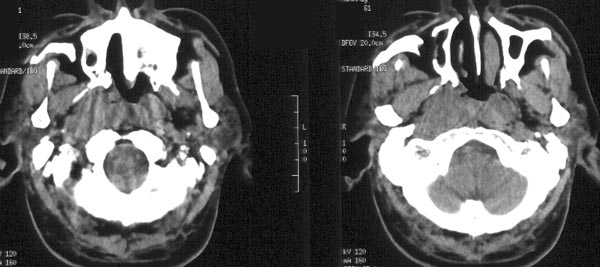

患者放疗后半年ct复查

ct平扫:鼻咽右侧壁增厚,右侧咽隐窝消失,右侧咽旁间隙变窄,但病灶较原片明显缩小。原片所见鼻咽顶壁、顶后壁、后壁增厚,现已基本恢复正常,原片见枕骨斜坡、蝶骨基底部骨质破坏,现亦已修复,为高密度骨质充填。颈深筋膜各间隙未见肿大淋巴结。

ct诊断:鼻咽癌放疗后,肿物较前片明显缩小,颅底骨质破坏基本修复。